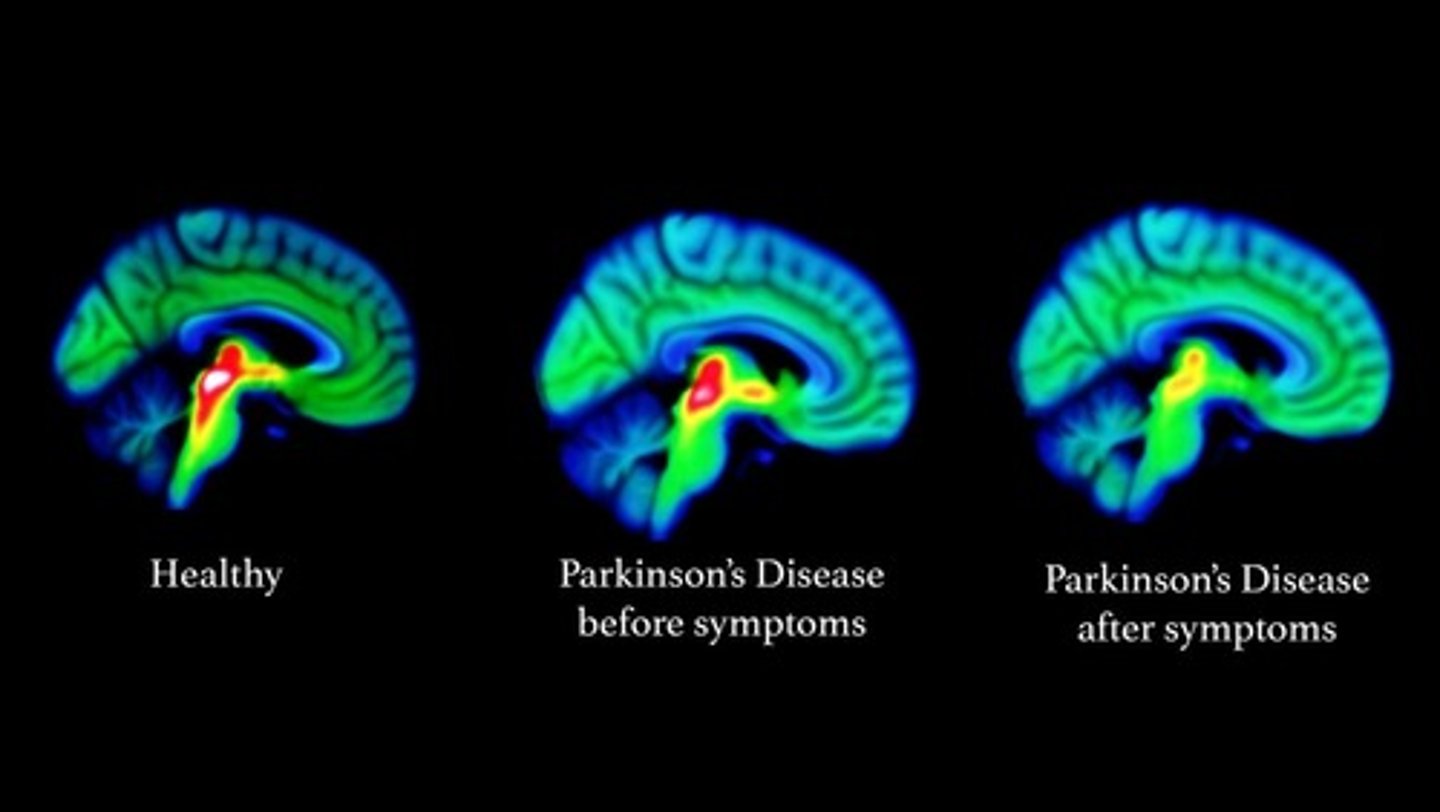

Basal Nuclei clinical: Parkinson's Disease

Results from degeneration of dopamine-releasing neurons, which causes the deprive basal nuclei they target to become overactive and produce the well-known symptoms of tremors at rest,

Cause still unknown, but may be environmental